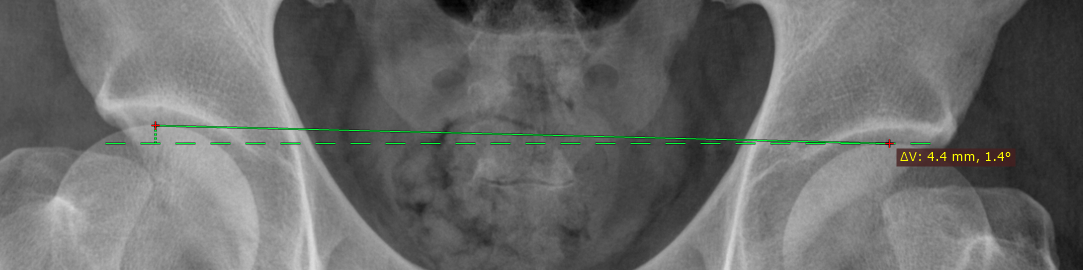

水平偏差测量

将显示两个测量值:

• 线段一端到与另一端相交的水平线(或垂直线)之间的垂直(或水平)距离(毫米)

• 线段与该水平线(或垂直线)之间的夹角(度)